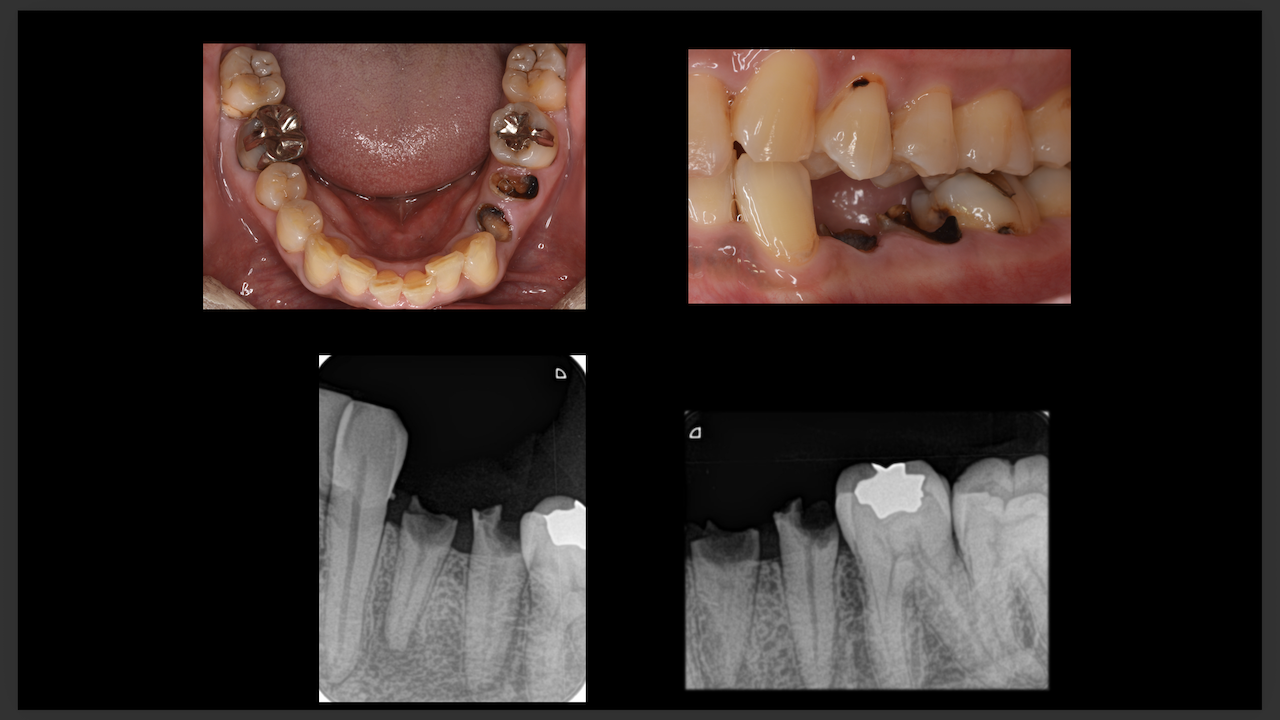

次が勤務医の立場でこのコースに来られたA先生。

エンド-ペリオ病変を有する歯の根管治療を発表していただいた。

ここから3ヶ月が経過した。